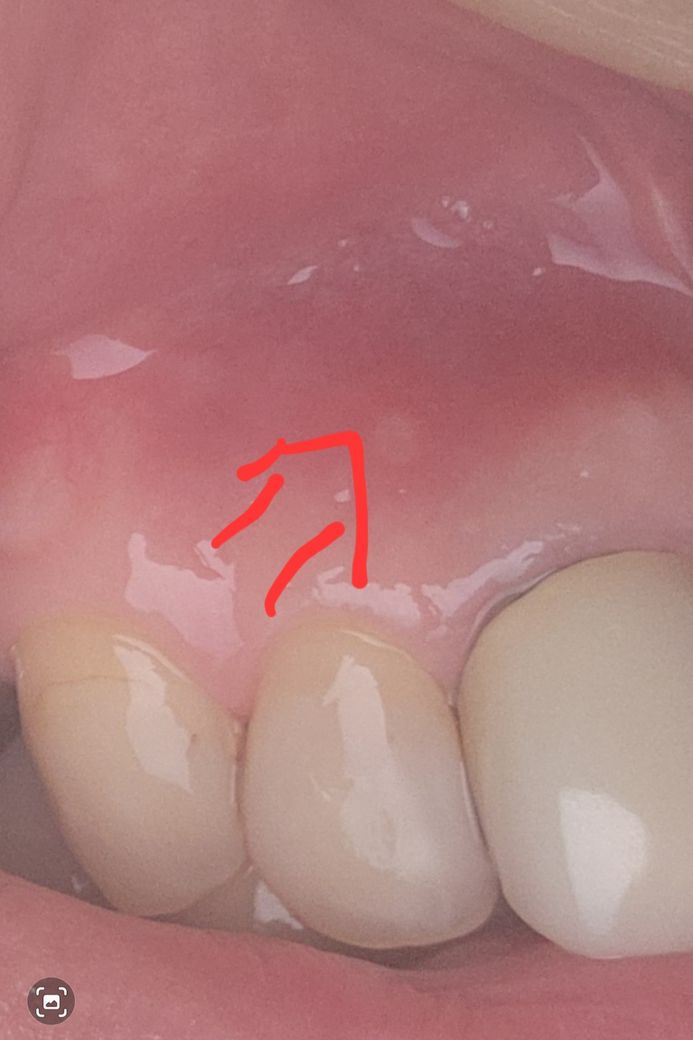

잇몸에 하얀색 점. 잇몸 염증일까요~? 치아 염증일까요~?

몇일전 양치를 하다가 잇몸 쪽이 따가워서 보니

잇몸에 하얀색 점이 생겨있었어요

1.잇몸 염증일까요~? 치아 염증일까요~?

2.바로 치과를 가야할지 어느정도 지켜봐야될지 여쭈어봅니다.

단순 구내염으로 보입니다. 없어지는 지 1주일정도 지켜보시고 더 커지거나하면 치과 가보시는 게 좋겠습니다.

치아의 염증은 아니고 저부위에 자극이 가해져서 잇몸이 구내염처럼 생긴거 같습니다. 시간이 지나면 괜찮아 지실꺼에요.

잇몸에 염증일 가능성이 높으며, 우선 크기가 커지지 않고, 붓거나 출혈이 있지 않은 경우에는 조금 더 지켜셔도 괜찮습니다.